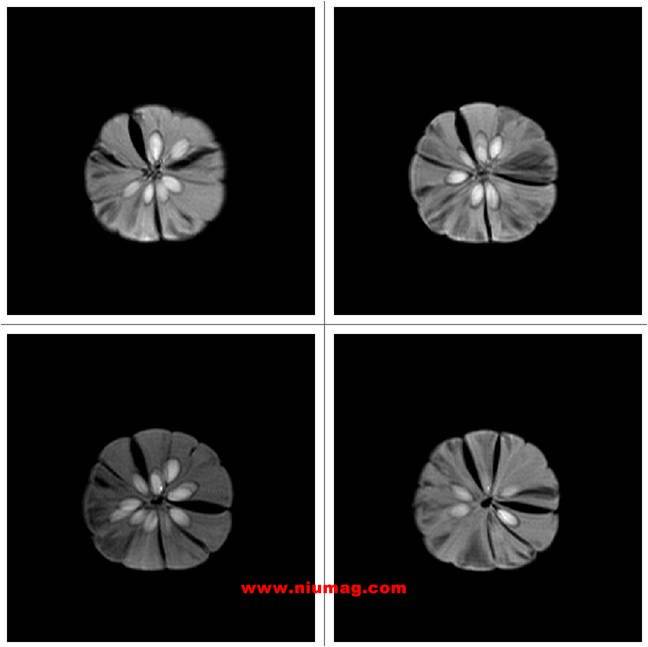

獼猴桃核磁共振多層成像圖